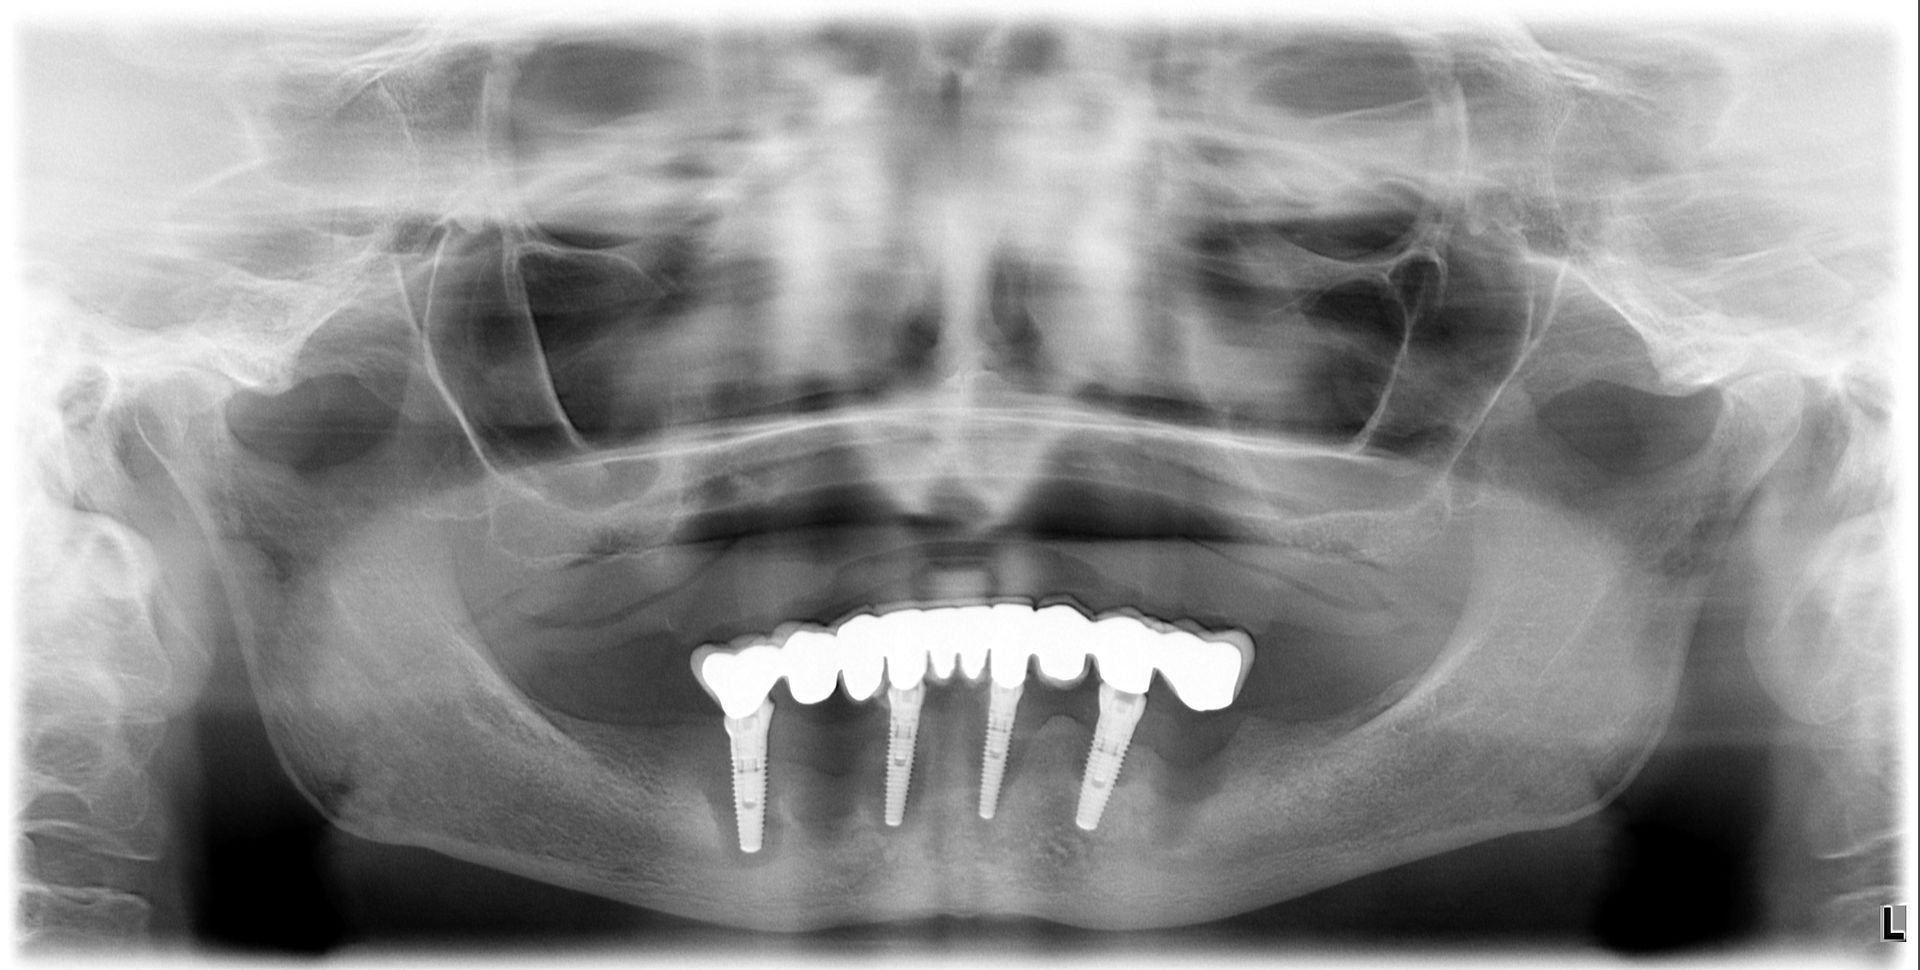

Il paziente era molto amareggiato perché non tollerava la protesi totale e aveva dolori dovuti agli impianti infetti dell'arcata inferiore. Dopo un attento studio del caso, in cui sono state studiate le forme e le altezze delle nuove protesi e abbiamo eseguito una pianificazione digitale dell'intervento chirurgico impiantare abbiamo inserito 5 impianti nel superiore con una rigenerativa orizzontale e 4 impianti nell'inferiore. a distanza di 4 ore dall'intervento abbiamo caricato gli impianti con le protesi provvisorie a carico immediato fatte con resina e una struttura in titanio, a distanza di 6 mesi sono state sostituite con 2 arcate titanio zirconio.